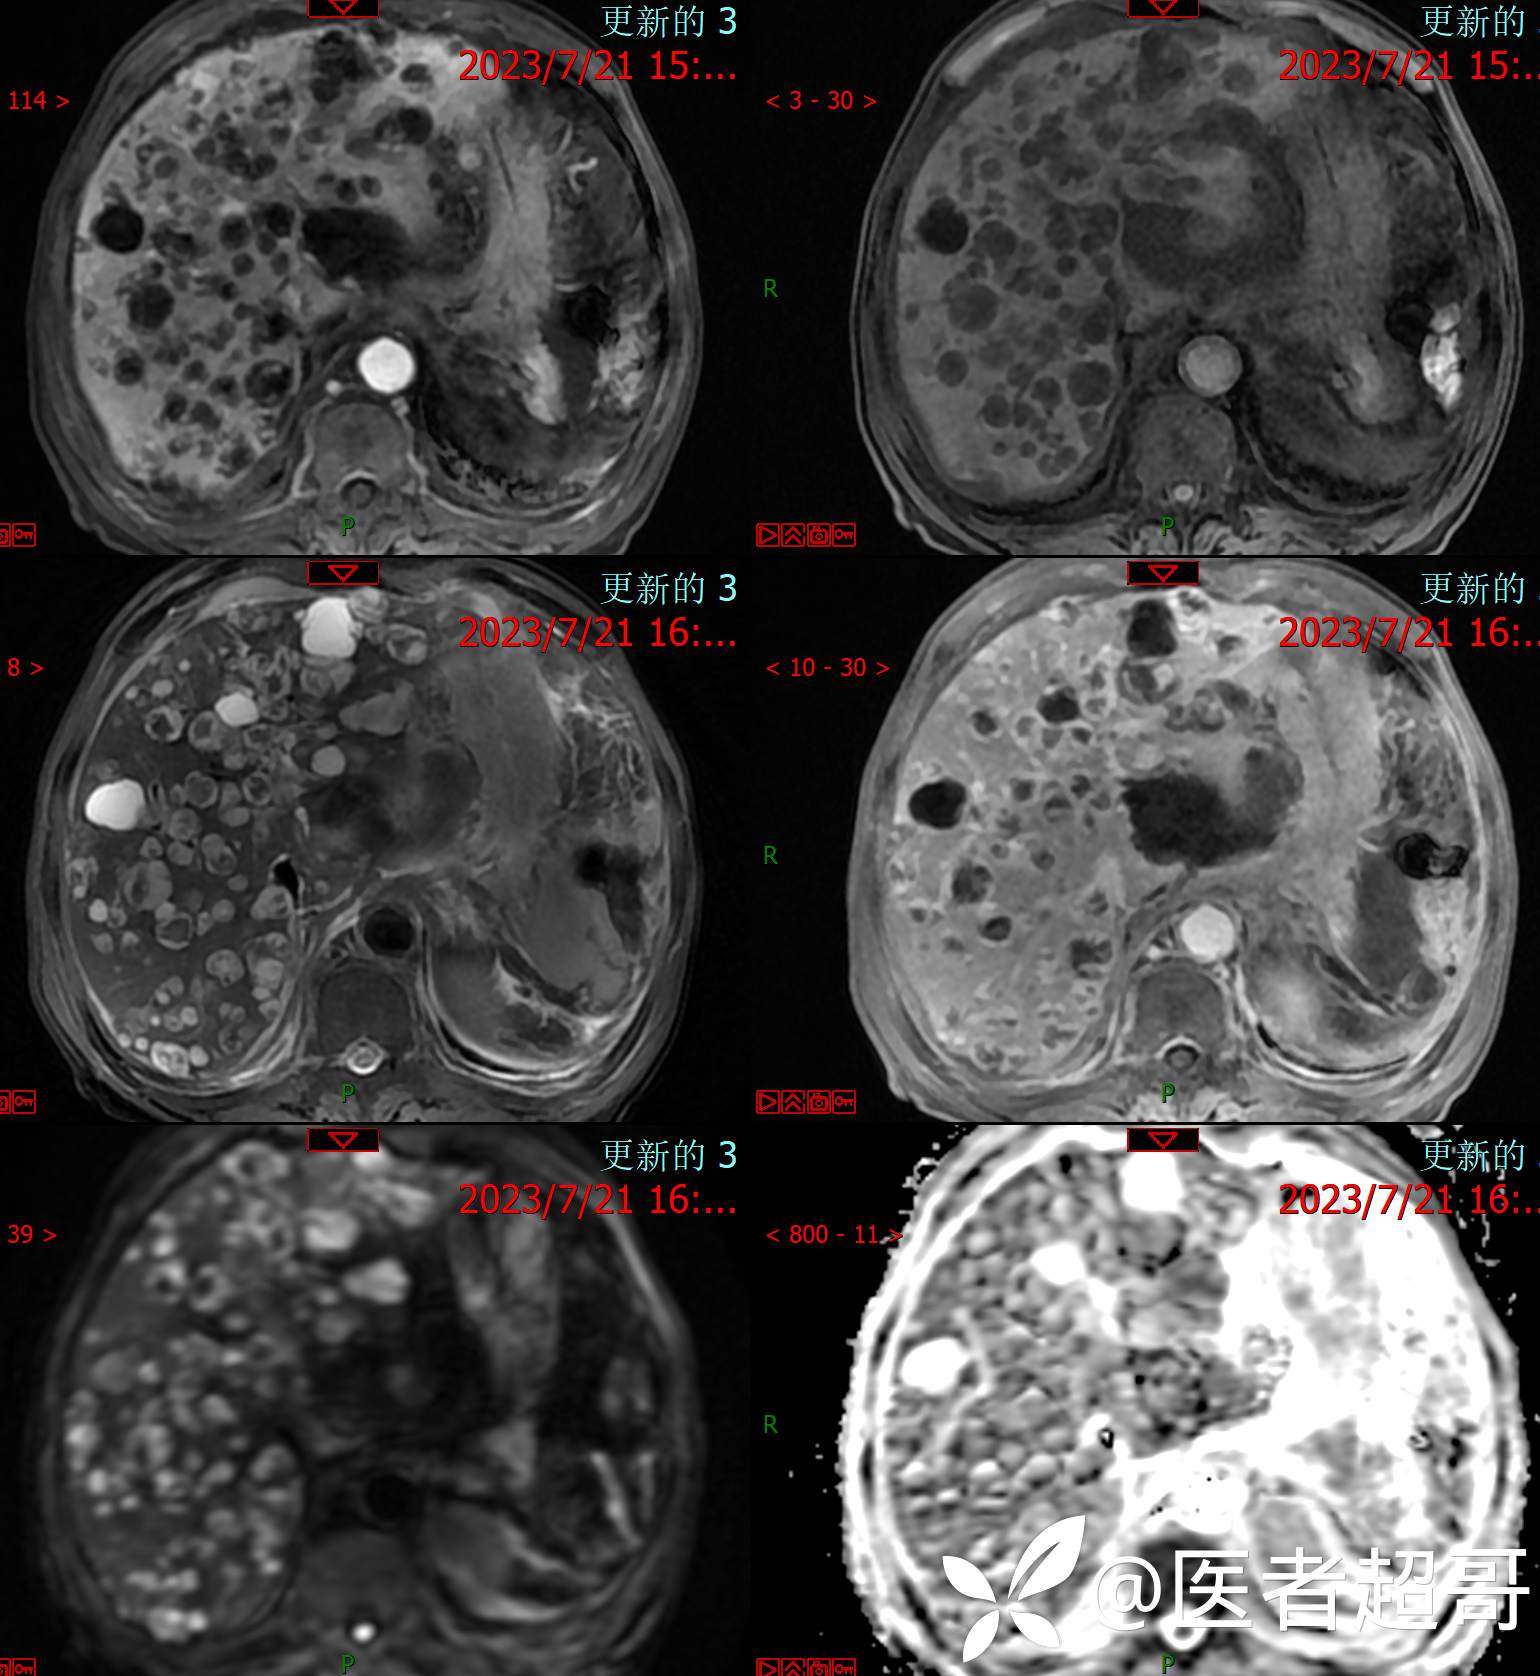

术后三个月复查CT、MRI表现: